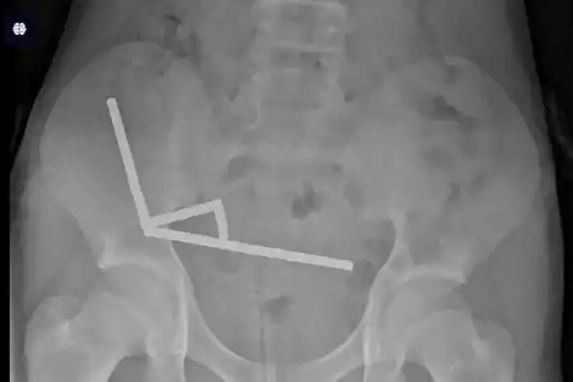

وأوضح الأطباء أن ابتلاع هذه المغناطيسات يشكل خطرًا كبيرًا، إذ قد يؤدي إلى تلف الأنسجة أو انثقاب الأمعاء وظهور التهابات داخلية، مشيرين إلى أن سهولة شراء هذه المواد عبر الإنترنت تمثل مصدر قلق متزايدًا للأسر.

وتعافى الطفل وغادر المستشفى بعد ثمانية أيام، فيما جدد الأطباء تحذيرهم من مضاعفات خطيرة قد تنتج عن ابتلاع مغناطيسات قوية، داعين إلى تشديد الرقابة على بيعها للأطفال عبر المتاجر الإلكترونية .